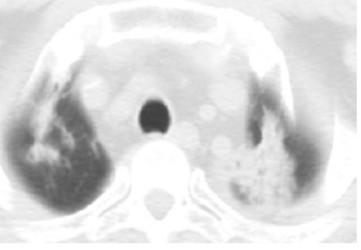

典型RILI影像表现及射野

WUj2fvhRjYOMcNYU.jpg EUuSa662a6s4XYS0.jpg

放射野内斑片影